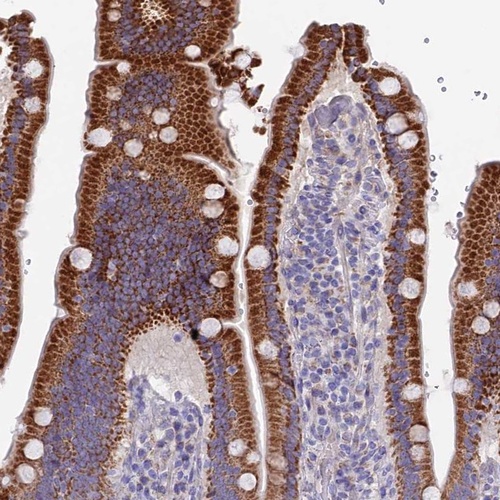

Immunohistochemistry analysis in human duodenum and pancreas tissues using Anti-ETFDH antibody. Corresponding ETFDH RNA-seq data are presented for the same tissues.